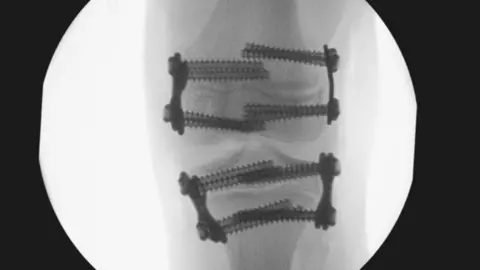

It raised concerns that surgeries were carried out on Amy’s knees when she was nine, and her legs were still growing.

But the assessment said metal plates inserted into her longer leg to stop it growing were too big, causing pain and requiring replacement.

Hudgell Solicitors with permission from Amy’s familyAmy’s right leg was then allowed to grow too much and ended up 3cm longer than her left.